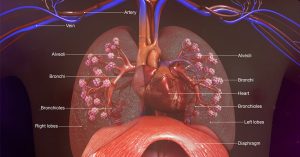

Respiratory system/tract is made of the following three parts: airway, lungs, and muscles of respiration known as diaphragm. The airway consists of parts that include the nose, mouth, pharynx, larynx, trachea, bronchi, and bronchioles which end in tiny sacs in the lung called alveoli. The air that we breathe passes through the nose or mouth through the respiratory tract to the smallest bronchioles, and fills the alveoli that perform the function of gaseous exchange. The airway up to the larynx is called upper respiratory tract. The alveoli are supported by a lace like structure in the lungs known as interstitium. It also contains blood vessels for exchange of air with the alveoli. The lungs are surrounded by a soft double layered covering called the pleural membrane, which contains a fluid within, called the pleural fluid. The space between the membranes is called pleural cavity. The cells that line the pleural cavity are known as mesothelium.